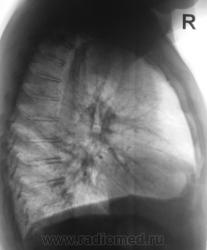

А где это все на боковой? Зато аорте какая красавица! Может это она и есть?

А может это праволежащая аорта?

Да, вроде как dextra-позиция аорты, под скопией бы глянуть.